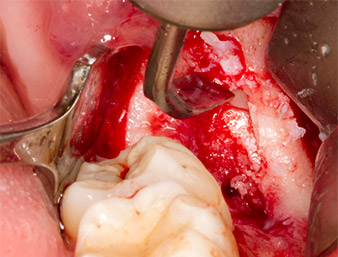

After block and local anaesthesia, the operating site was opened up and the soft tissue exposed for buccal retromolar access (Fig. 3).

The tissue above the root remnant was not completely ossified and consisted for the most part of granulation tissue modified by inflammation (Fig. 4).